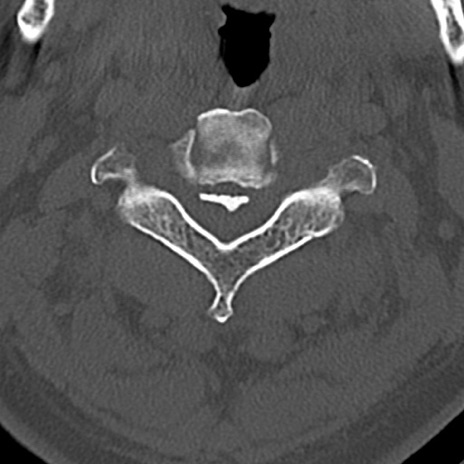

頚椎CT

横断像